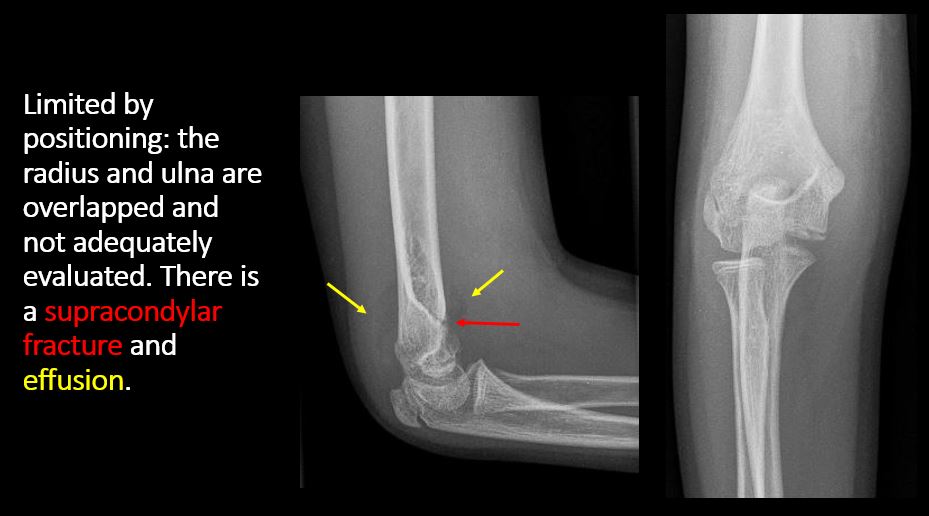

The exam is limited by overlying structures or soft tissues, body habitus, patient positioning, support devices, or motion. [Yes/No]

There is an effusion, fat pad displacement, or fat fluid level. [Yes/No]

There is disruption of commonly recognized anatomical lines (e.g. iliopectineal, radiocapitellar, anterior humeral) or structures (e.g. sacral foraminal or arcuate lines). [Yes/No]